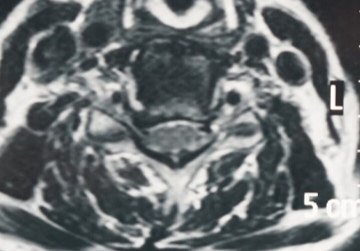

患者颈部及右上肢疼痛麻木,经过数周保守治疗无好转。诊断为神经根型颈椎病,颈56椎间孔狭窄。行颈椎经皮内镜下椎间孔扩大成形术,术后患者疼痛麻木明显好转。